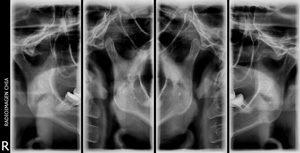

Radiografía extraoral para evaluar la articulación temporomandibular en cuatro cortes (boca abierta y cerrada). Fundamental para diagnosticar alteraciones, chasquidos o trabas en la mandíbula.